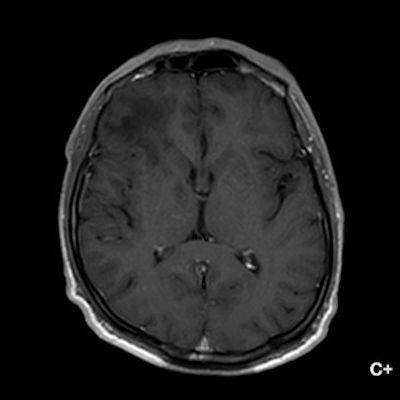

1. A) Aksiyel T2A görüntülerde bilateral sağda belirgin frontoparietal subkortikal ve derin periventriküler beyaz cevherde subkortikal U fiberleri boyunca yerleşimli sinyal artımları (oklar) izlendi.  Tarifli alanlar aksiyel T1A serilerde hipointens görünümde (oklar) izlendi.

2. B) Aksiyel diffüzyon ağırlıklı serilerde bilateral sağda belirgin frontoparietal subkortikal ve derin periventriküler beyaz cevherde periferal DAG hiperintens ADC hipointens, hafif diffüzyon kısıtlaması (oklar) eşlik etmektedir. IVKM sonrası kesitlerde tarifli alanlarda belirgin kontrast tutulumu (oklar) izlenmedi.

1. PML’de MRG bulguları genellikle multifokal, asimetrik periventriküler ve subkortikal beyaz cevher tutulumu şeklindedir. Subkortikal U-fiberleri sıklıkla tutulur, özellikle parietooksipital bölgelerde belirgin lezyon eğilimi vardır.

2. T1 ağırlıklı görüntülerde tutulan bölgeler hipointens, T2A’da ise hiperintens izlenir. Ana lezyon çevresinde çok sayıda noktasal (milkyway) sinyal artımları görülebilir. Ayrıca spleniumu çaprazlayan parietooksipital sinyal değişiklikleri (barbell bulgusu) ve dentat nukleusu koruyarak serebellar beyaz cevher tutulumu (shrimp bulgusu) da tanımlanmıştır.

3. Kontrastlı incelemelerde genellikle kontrast tutulumu izlenmez. Diffüzyon görüntülemede özellikle lezyonun ilerleyen periferik alanlarında yamalar halinde diffüzyon kısıtlılığı izlenir. MR spektroskopide NAA azalması, laktat varlığı ve artmış kolin ve lipid düzeyleri görülür. MR perfüzyonda ise lezyonların ilerleyen kenarında perfüzyon artışı saptanabilir.

4. Bizim hastamızda bilinen HIV enfeksiyonu mevcuttu ve yapılan kraniyal MR görüntülemede multifokal, asimetrik, periventriküler ve subkortikal beyaz cevherde yerleşimli, kitle etkisi göstermeyen ve kontrastlanmayan lezyonlar izlendi. Lezyonların subkortikal U-fiberleri tutması ve özellikle parieto-oksipital bölgelerde belirgin olması nedeniyle ön planda PML düşünüldü. Histopatolojik tetkik ile PML tanısı doğrulandı.